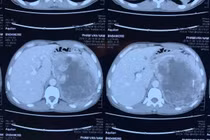

(khoahocdoisong.vn) - Nhờ sự chuyển giao kỹ thuật từ Bệnh viện Việt Đức và Bệnh viện Bình Dân, khoa Ngoại Tiết niệu - Bệnh viện Đa khoa tỉnh Thanh Hóa đã thực hiện rất nhiều kỹ thuật cao, kỹ thuật chuyên sâu chuyên ngành Tiết niệu và Nam học, cứu sống nhiều người bệnh. Một người bệnh có khối u tuyến thượng thận khổng lồ vừa được phẫu thuật thành công nhờ chuyên môn cao và thiết bị hiện đại.